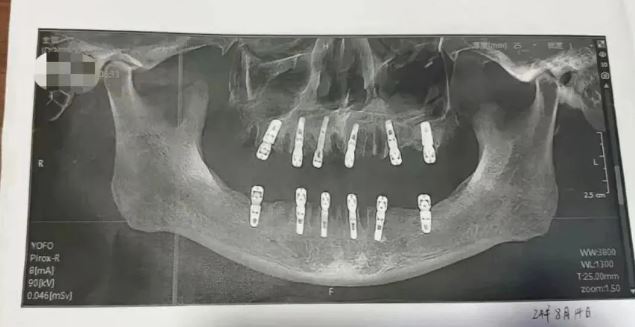

中媒《现代快报》引述舒女士发布的信息显示,其父亲黄某8月14日在德维口腔医院接受牙科手术。根据种植手术同意书显示,本次治疗拔牙23颗、种植牙齿12颗,并且均为即刻修复,即“当天拔、当天种”,负责进行治疗的医生为袁某。

在结束种植牙手术后,黄某牙齿一直疼痛不止,并于8月28日因心脏骤停死亡。